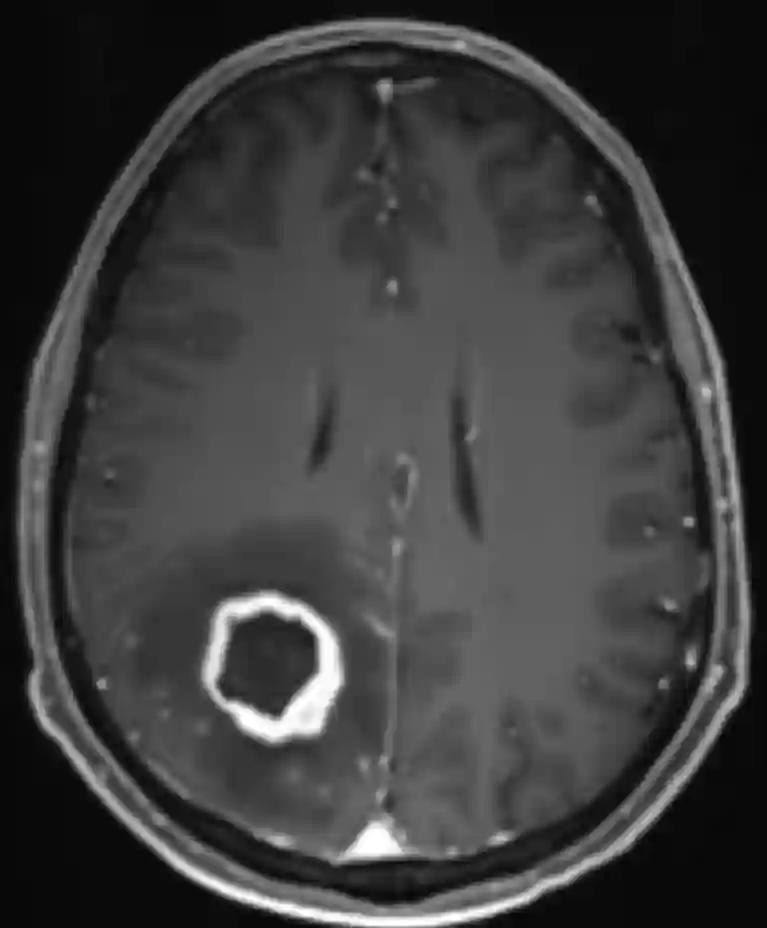

Aspergillom im MRI

Darstellung eines histopathologisch gesicherten Aspergilloms in einer axialen T1 Sequenz mit Kontrastmittel lokalisiert parietal auf der rechten Seite.